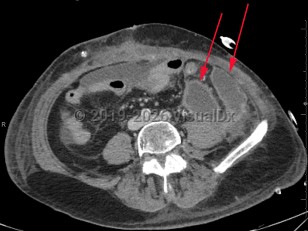

Intraabdominal abscess

A collection of pus located inside the abdominal cavity that forms as a result of inoculation of one or more pathogens into a normally sterile intraabdominal location.